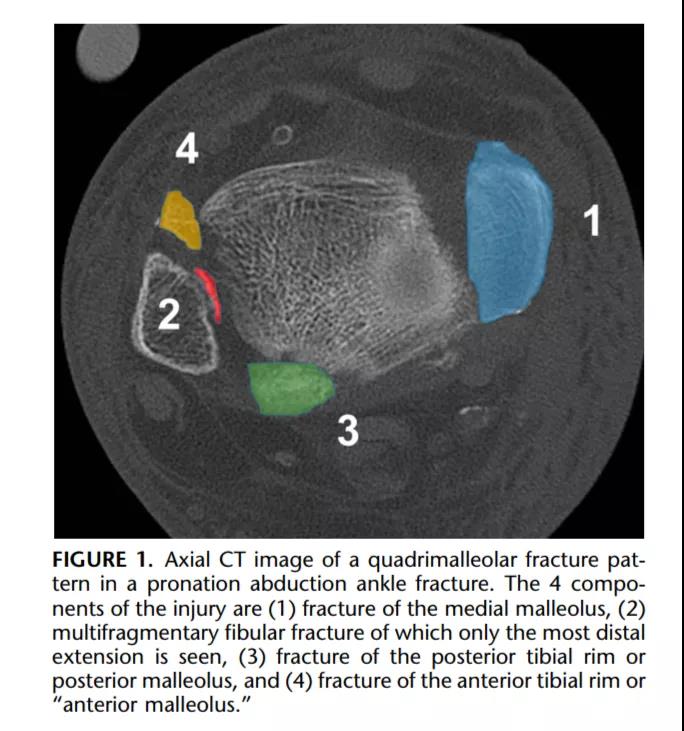

① 四踝骨折示意图:1.内踝;2.外踝;3.后踝;4.胫骨前结节(前踝)。